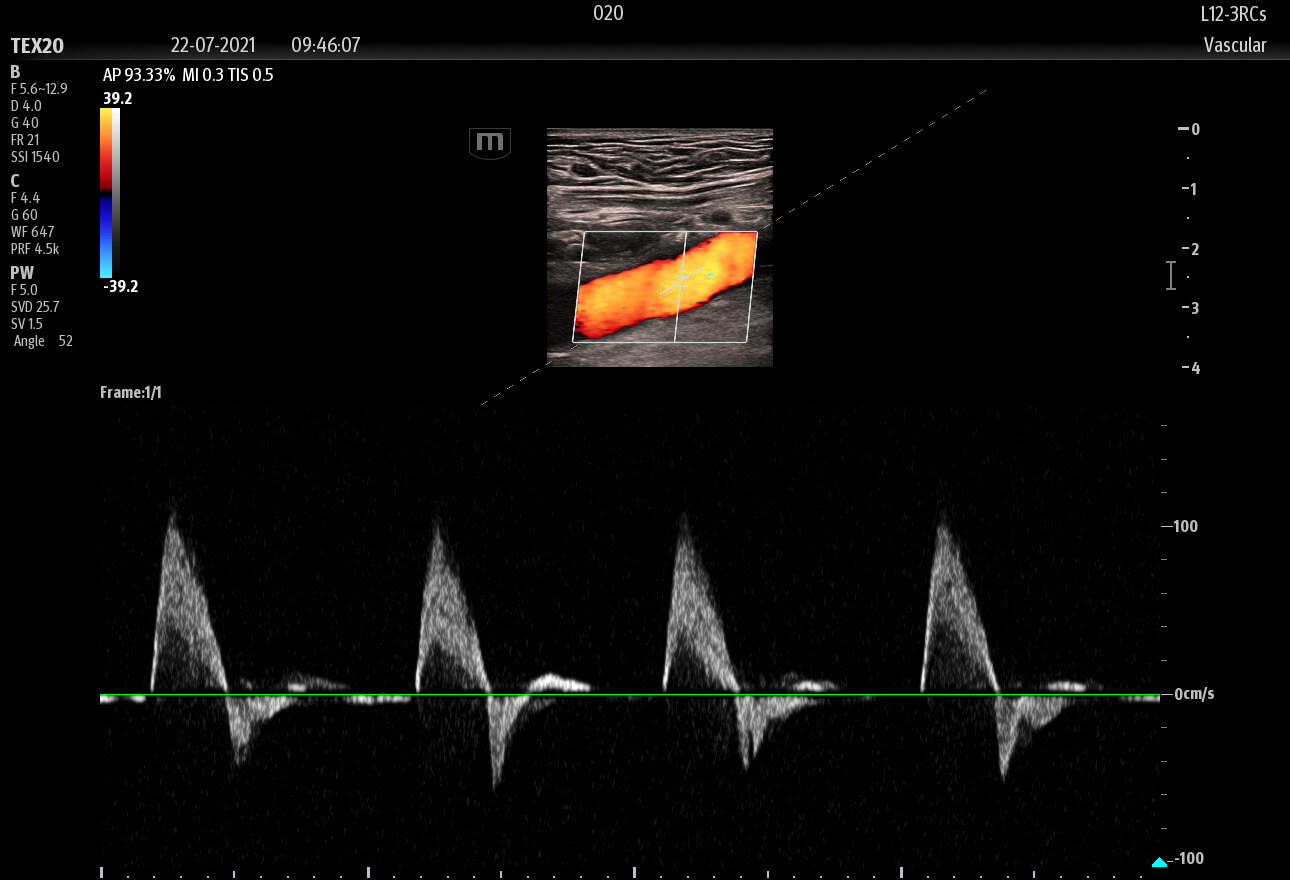

The technology-rich TE X Ultrasound System gives clinicians access to market-leading artificial intelligence (AI)-powered Smart Tools, an ergonomically designed system, and proprietary software-based beamformer Zone Sonography Technology+ (ZST+). By incorporating these elements, the TE X Ultrasound System provides access to advanced diagnostic data, the ability to adapt to the various clinical scenarios at point of care, and best-in-class imaging to help them provide a higher standard of care.